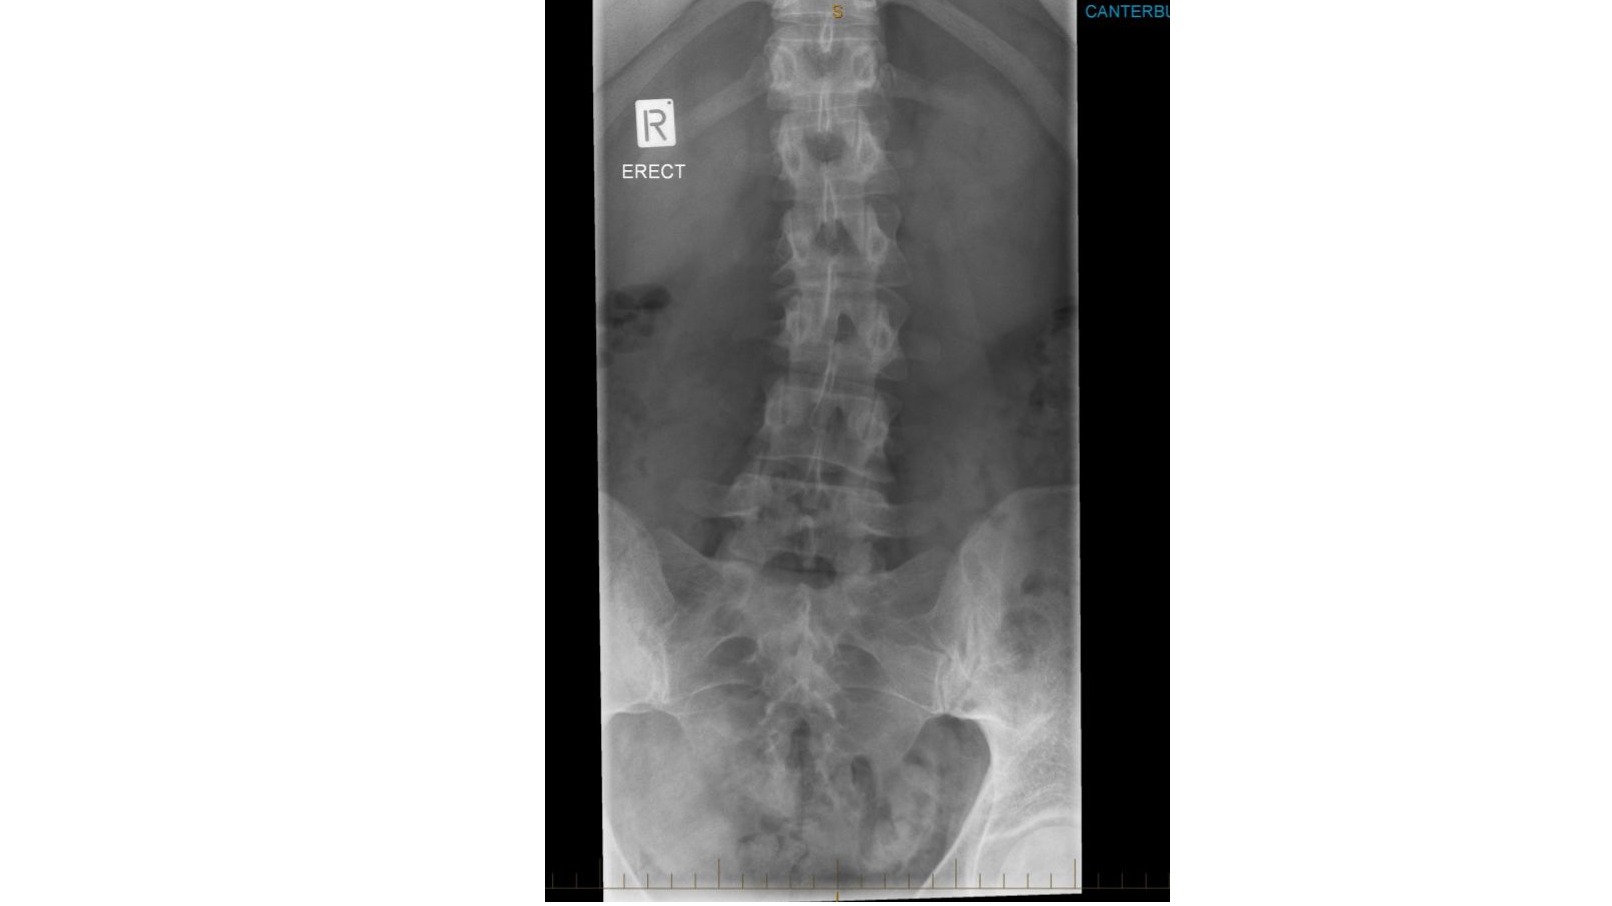

Hello my name is Krista Bain When I was a teenager I was in a incident where I came of a sprinting horse. The horse flwe me in the air and I landed crash down on my back with a 'crunch' sound in my spine. I felt tingling in my legs and adrenaline kicking in. I was so afraid. I was in shock unable to get up or move. I waited what felt to hours pass by and managed to slowly grasp myself to a stand. When I arrived back to to the horse stable I told the people there what happened. They comforted me and let me call my caregiver( I will not make the person to there discression)They knew the horse I was riding was not tame as did I but I regretfully chose to ride this horse regardless.I was instructed to go to hospital and tell my caregiver to take me there.The drive was around 45 mins from home and longer to the hospital Because I had come off horses many many times in the past my caregiver decided to make the decision not to take me to the hospital to be examined. I was in alot of pain stopped riding and took weeks off school. Because of this eventually my caregiver took me to a medical centre but when I spoke she downplayed what I said out of embarrassment of not providing my care at the time and I left that appointment deviated and without any Acc claim or examination. I have finally received a doctor after many attempts for x-rays that went unnoticed be ause I didn't receive a claim to begin with. The x-ray shows L2 &L1 fractures that have healed and a concaved scelrosis of the lower spine. The pain has only gotten worse over the years and without nerve pain killers 5 times per day I'm in absolute agony. I am afraid to take these pills for the rest of my life. I am unable to receive any help for surgery from Acc because this is a past incident. I have not been able to keep any work because my pain get heightened with any form of physical work. I am afraid of ending up in a wheelchair when I am older and having to take nerve painkillers for the rest of my life. I have a six year old son and I really cannot bare the thought of the future going downhill like this. I am afraid of being stick for the rest of my life due to the neglect of my caregiver. I have big dream to accomplish I have a great voice, I was a champion at netball and I love animals horseriding and travel. I feel down and out and the pain is closing off my ability to speak up and to get out and do things I would usually enjoy. I want to be a great role model for my son and work a great deal and provide the life for myself and my son so he can have a good future as well. I need to raise $21,000 for a lower spinal infusion surgery to be able to get this done. I would greatly appreciate any help and I thankyou ? Krista